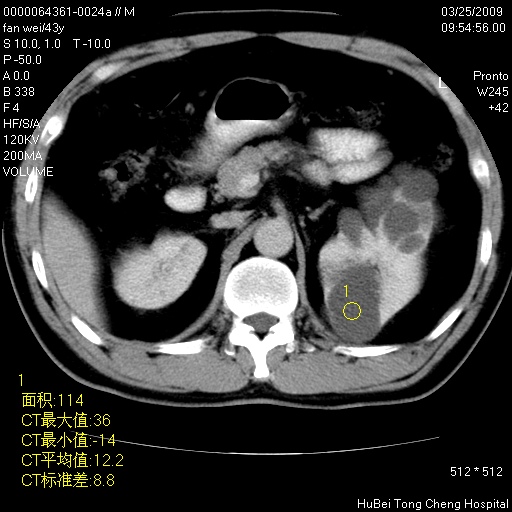

双肾ct轴位平扫+增强扫描(层厚10mm,螺距1.0,重建间隔10mm),图像如下:

多囊肾的影像诊断标准:有阳性家族史,年龄<30岁,单侧或双侧肾脏有两个肾囊肿;30~59岁,两侧肾脏各有两个肾囊肿;60岁以上,每侧肾脏有4个囊肿。敏感性和特异性达86%和80%。

此病例影像诊断符合,要结合家族史,腰痛、血尿、尿路感染史,有无高血压等综合判断,如无相应的临床症状,本身病变也无意义了(个人观点)

囊肿数得清,肾功能正常,考虑多发肾囊肿.另外,右肾后极突向肾周间隙的那个病灶是不是错构瘤,请楼主调窗看看.